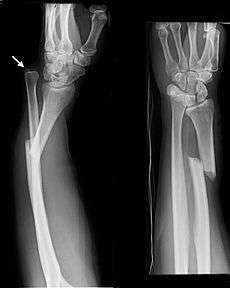

![]() Galeazzi fracture. Arrow points at the dislocated ulnar head | |

The Galeazzi fracture is a fracture of the radius with dislocation of the distal radioulnar joint. It classically involves an isolated fracture of the junction of the distal third and middle third of the radius with associated subluxation or dislocation of the distal radio-ulnar joint; the injury disrupts the forearm axis joint.[1]